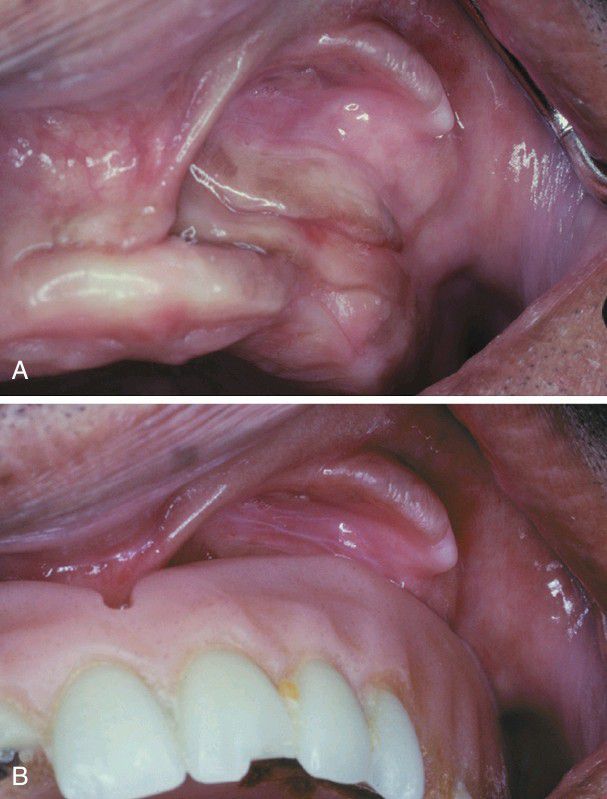

Epulis Fissuratum

A, Several folds of hyperplastic tissue in the maxillary vestibule. B, An ill-fitting denture fits into the f issure between two of the folds.